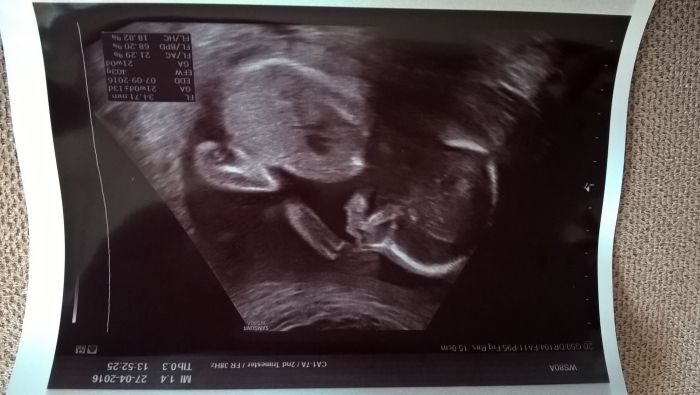

Ahoj holky, kdepak jste všechny? Já se hlásím z druhého velkého screeningu. Podle něj je vše v pořádku. Plodové vody je přiměřeně, placentu mám vlevo. Je to opravdu holčička, odpovídá 21+1 a dneska měla 403g. Viděli jsme jak si strká nožičku do pusinky... :-)

Nevím proč, ale zase se mi ty obrázky otočily... :-(